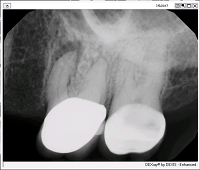

A 65-year-old white female presented for six-month follow-up after non-surgical root canal treatment on #14 completed by an endodontic resident. The patient reported unremitting pain (8/10) that occasionally worsens of its own accord. She also noted localized swelling of the gingival tissue and pain with flossing around tooth #14 several times in the last three months.

Hx Current Illness: #14 RCT was completed 6 month ago. Pre-op diagnosis was pulpal necrosis and symptomatic apical periodontitis. She had initially presented with mild intraoral swelling, which resolved after treatment. Patient reports that the nature of pain has changed since the root canal has been completed but has not resolved. Now, the pain has a radiating and pulsating quality.

Radiographic assessment is suggestive of a 1-mm overextension of obturation material. A post-operative CBCT scan suggests that no separate MB2 canal is present. Post-operative imaging is suggestive of periapical bony healing around MB root of #14. However, the buccal plate remains perforated. No sinus membrane inflammation noted. Remainder of CBCT scan is unremarkable.